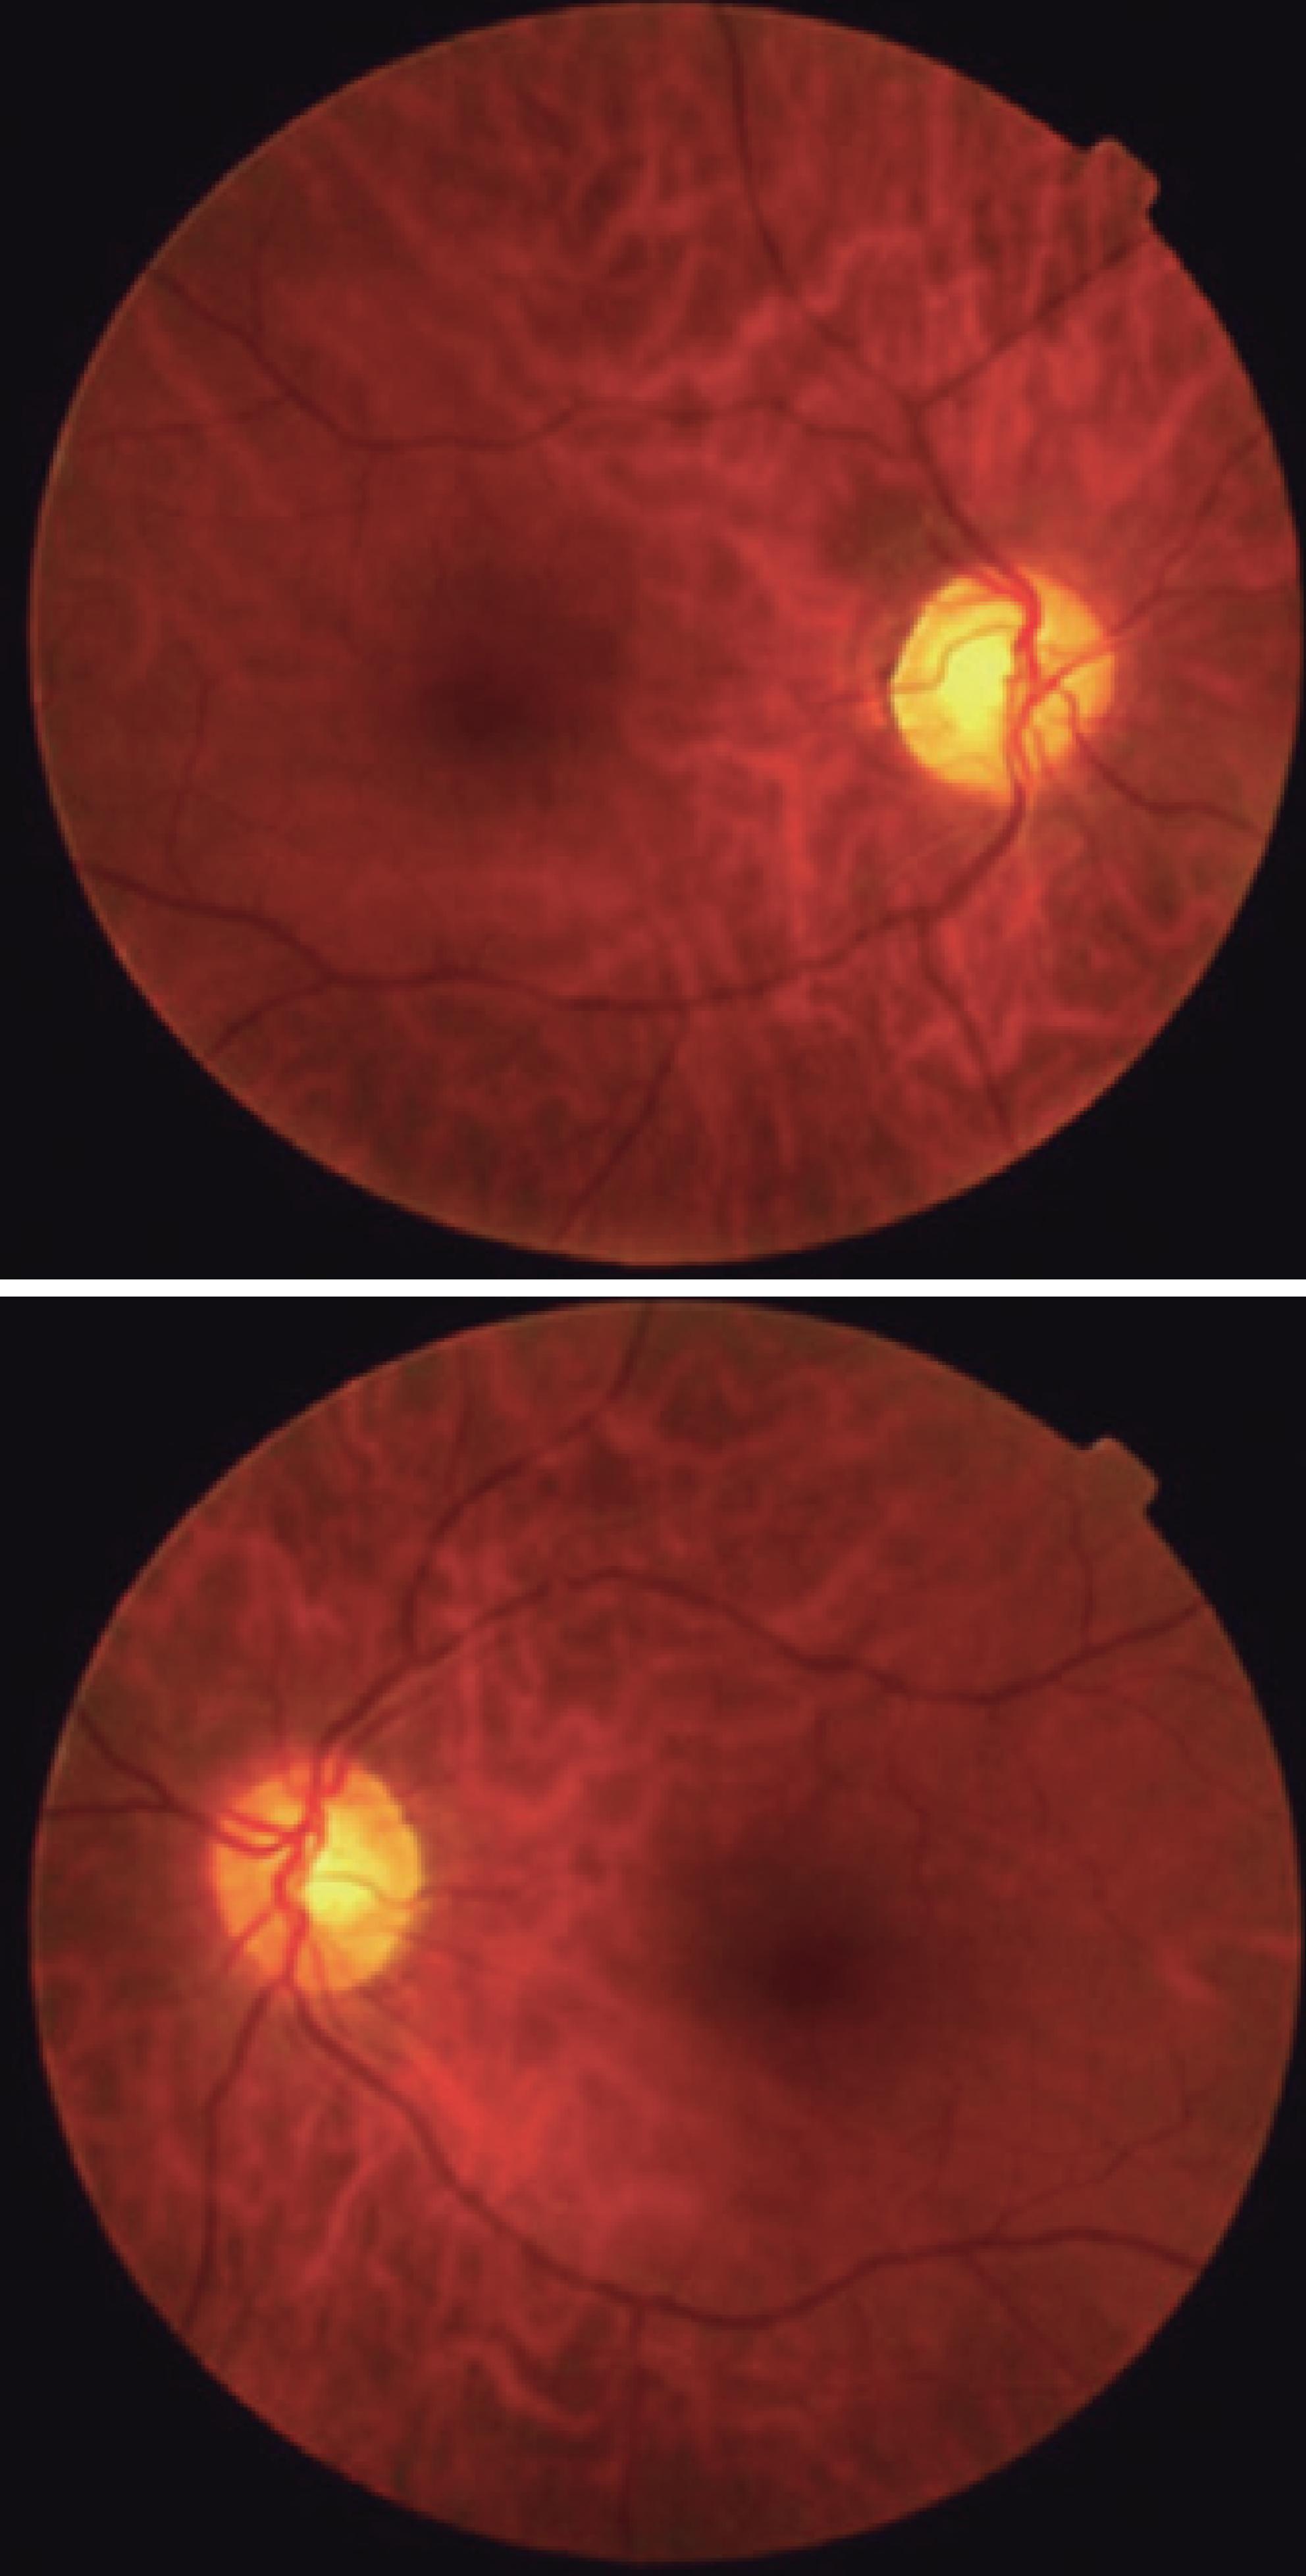

On admission, physical examination revealed a blood pressure of 200/176 mmHg. His visual acuity was classified as “counting fingers” in both eyes, but one hour later it deteriorated to “no light perception” in both eyes. The eye fundus examination was normal (Figure 1). The patient’s pupils were isochoric with a normal light reflex. Neurologic examination showed mental confusion and the electroencephalography revealed slow background activity and the loss of alpha rhythm in the posterior pole. Blood laboratory tests revealed no abnormalities. Electrocardiography and the chest X-ray were normal. An immediate computed tomography (CT) scan was negative for intracranial hemorrhage but showed dilation of the right occipital horn and moderate signs of cortical and subcortical atrophy. Magnetic resonance imaging (MRI) acquired 24 hours after admission revealed a cortical hyperintense lesion in the left cerebellar hemisphere and an enlarged right ventricle judged to be secondary to a previous infarct (Figure 2). In addition, apparent diffusion coefficient maps obtained during the PRES revealed increased diffusion in the occipital regions indicative of vasogenic edema (Figure 3).

Figure 1 Eye fundus of a 66-year-old man with posterior reversible encephalopathy syndrome. The funduscopic examination of both eyes was normal.

Visual disturbances are common in PRES, even in the absence of funduscopic abnormalities(5). In our case, the eye fundus examination was normal, indicating that the loss of vision must have been caused by changes somewhere else in the visual pathway. The presence of cortical visual symptoms remains a helpful diagnostic feature indicating occipital lobe involvement. Retinal or optic disc ischemia and papilledema have been implicated when patients have visual complaints(6), but occipital lobe involvement must be considered when the fundi appear normal or there are occasional visuospatial or speech disturbances(5). Typical visual symptoms range from a nonspecific blurriness with normal visual acuity to color-blindness, visual field defects, and even complete blindness. Visual hallucinations, the impairment of facial recognition (prosopagnosia), parietal lobe dysfunction with inappropriate behavior, the denial of blindness (Anton’s syndrome), and blindness with intact pupillary light reflex may simulate drug ingestion or withdrawal, complex migraine, or even a psychiatric illness. Isolated cortical blindness, as occurred in our patient, and occipital lobe seizures as a manifestation of hypertensive encephalopathy, have also been reported(7).